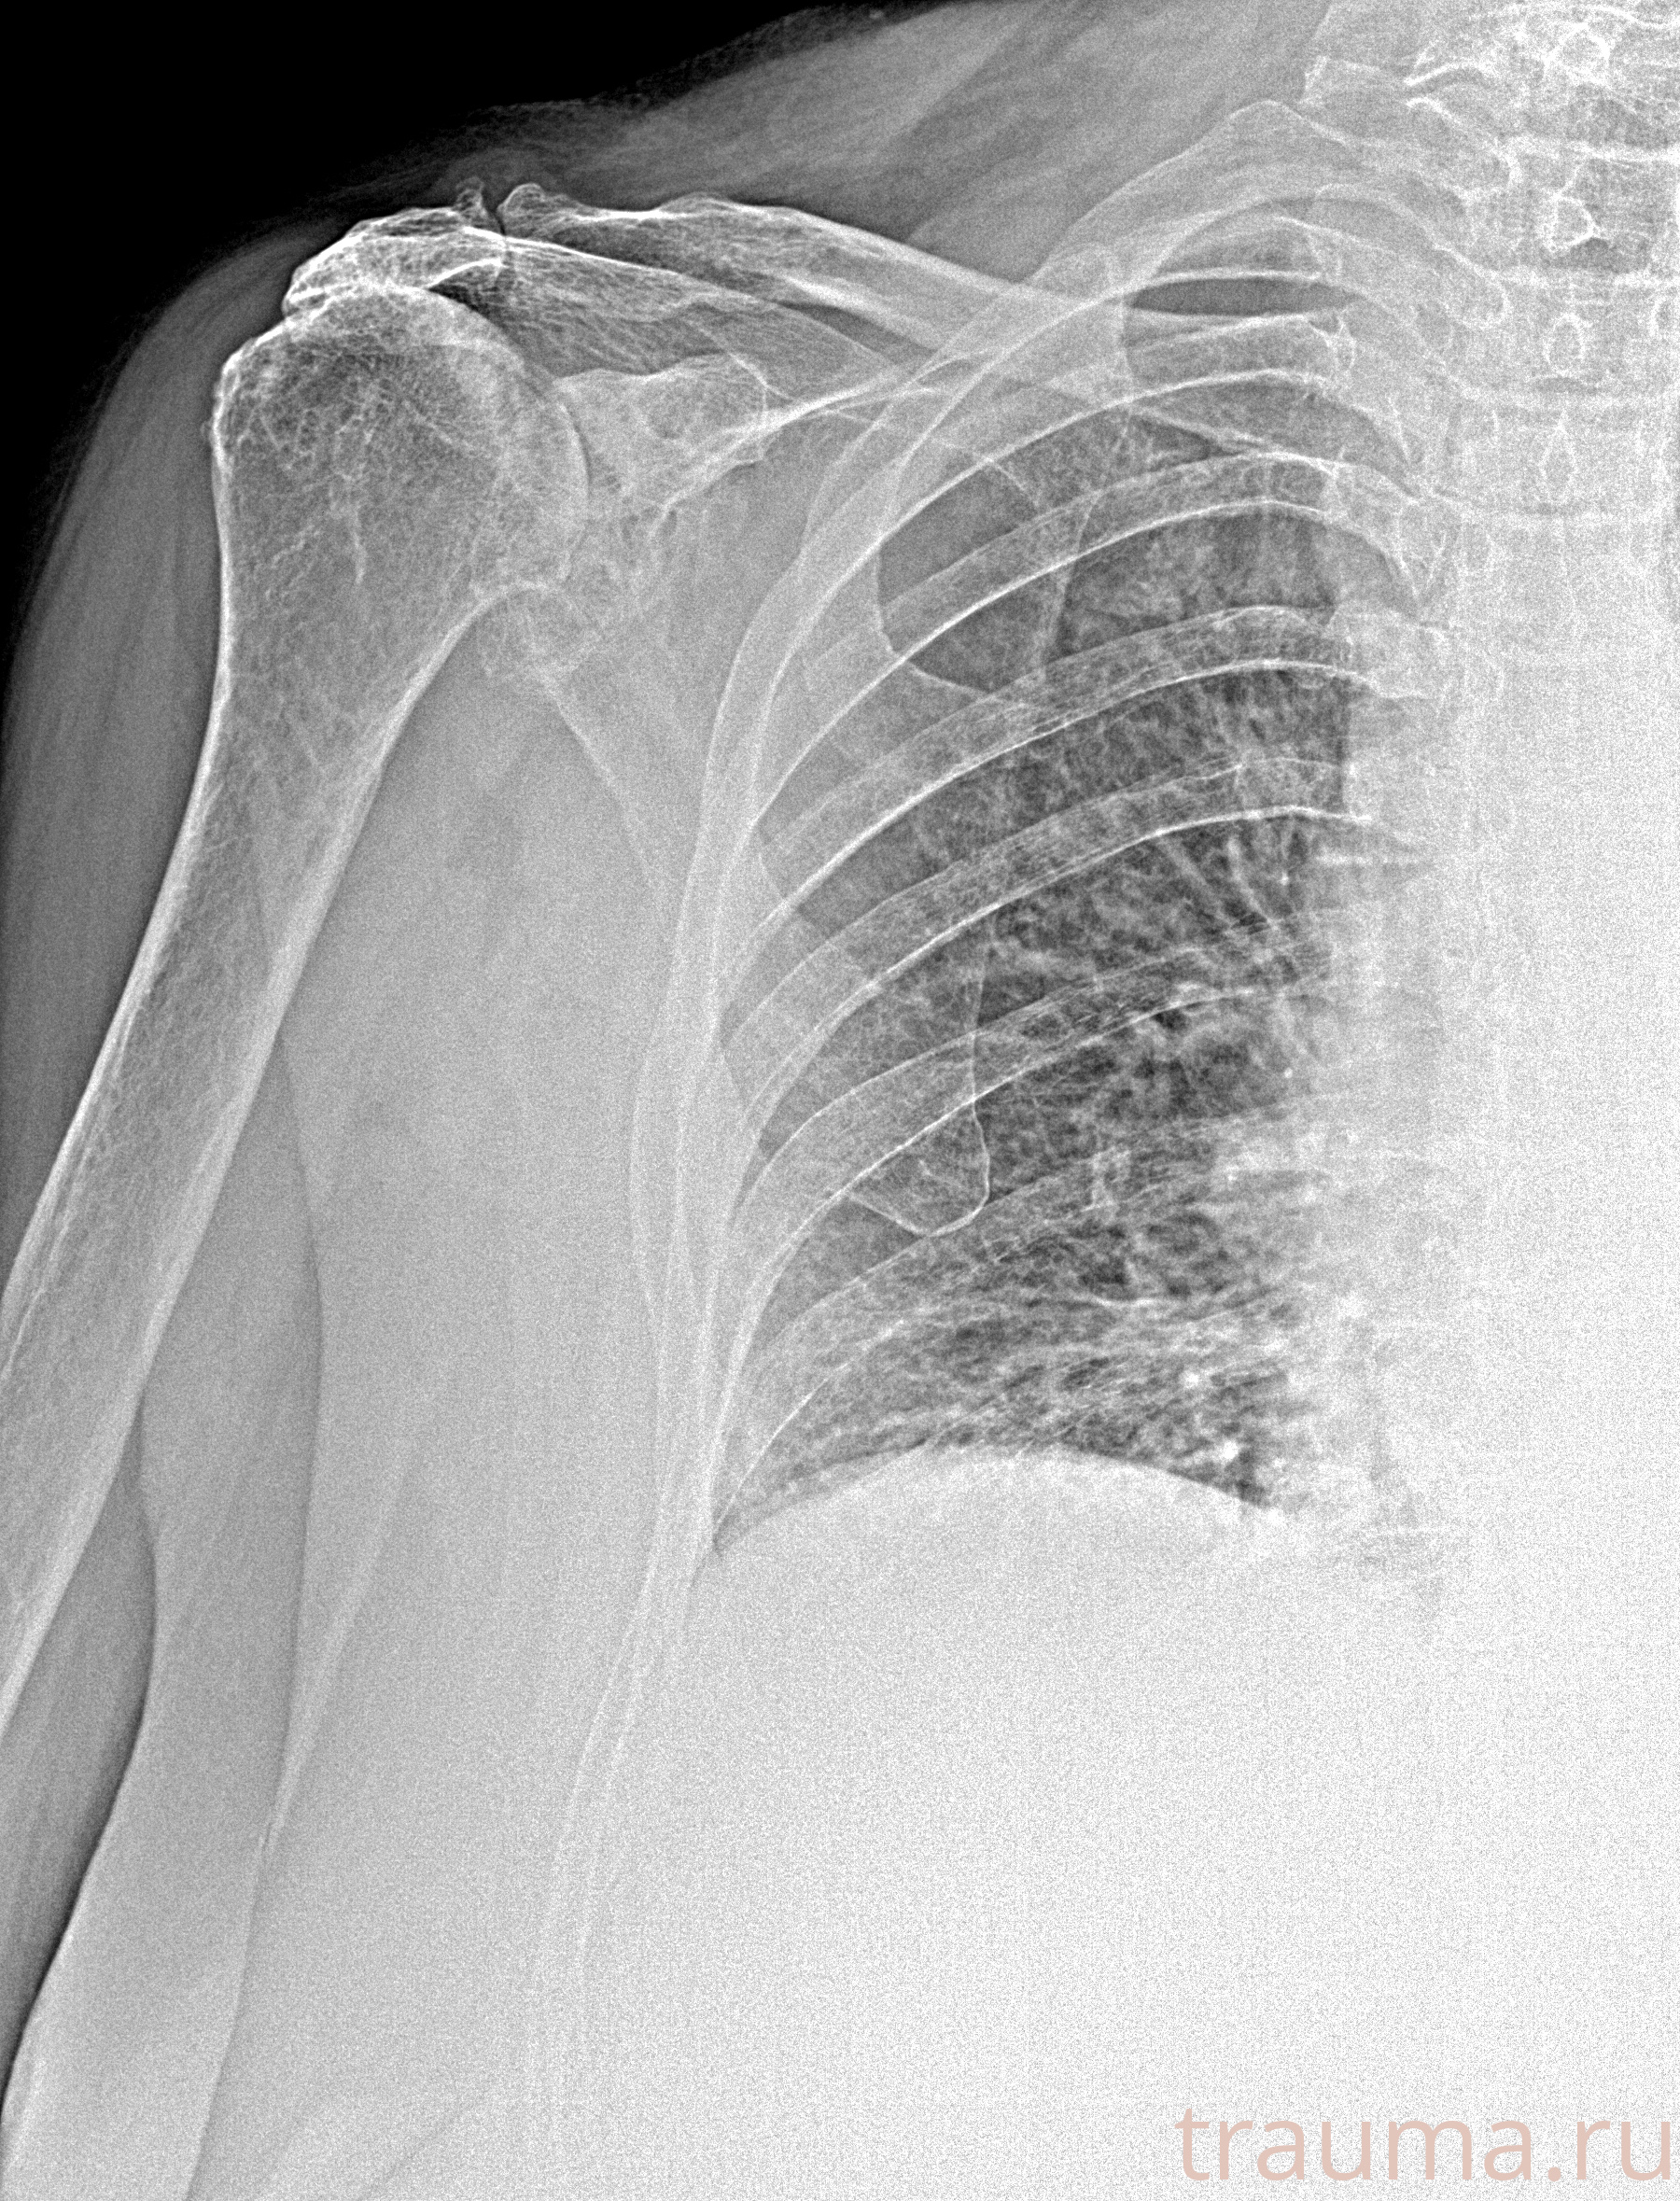

Рентген на дому: по вашему адресу приезжает врач-рентгенолог, травматолог-ортопед с мобильным рентгеновским аппаратом, проводит диагностику травмы или заболевания, делает необходимые рентгенограммы, дает рекомендации по дальнейшему лечению. Получить качественные снимки в домашних условиях возможно благодаря уникальной методике, разработанной МосРентген Центром для института  Склифосовского